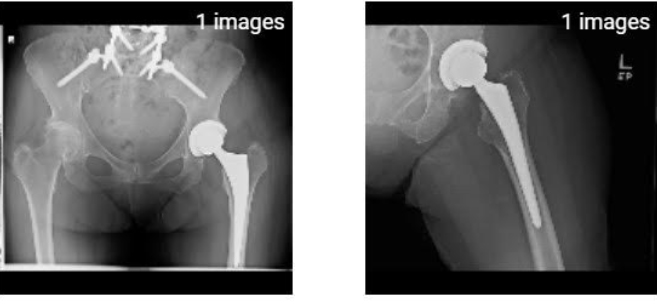

I still am doing the 4 mile hike. So with 3 times a week at PT and the hike my days are busy. Hope we can get started with our summer by Easter. Here are two views of my spine at my one year checkup.

Here are my January 2022 x-rays